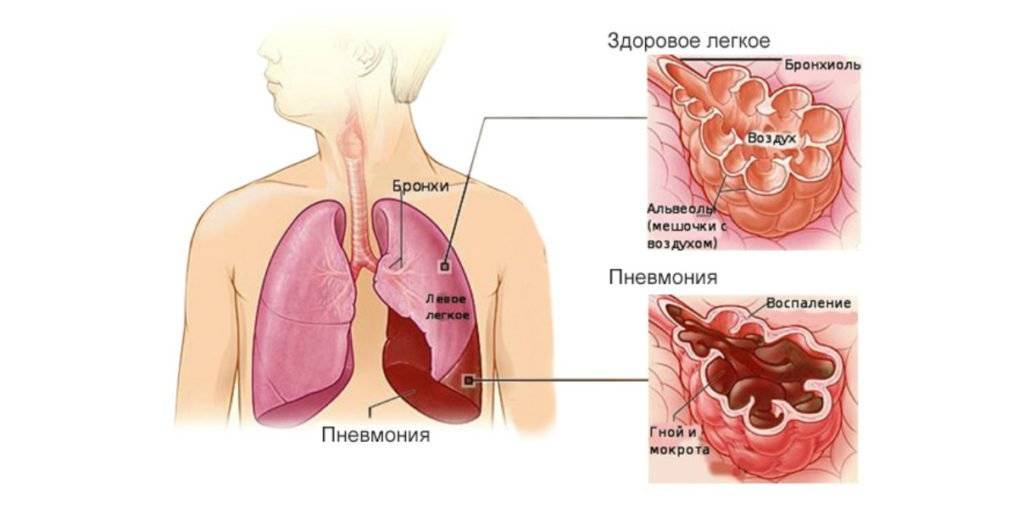

Фотографии бактерий, вызывающих бактериальные пневмонии у животных